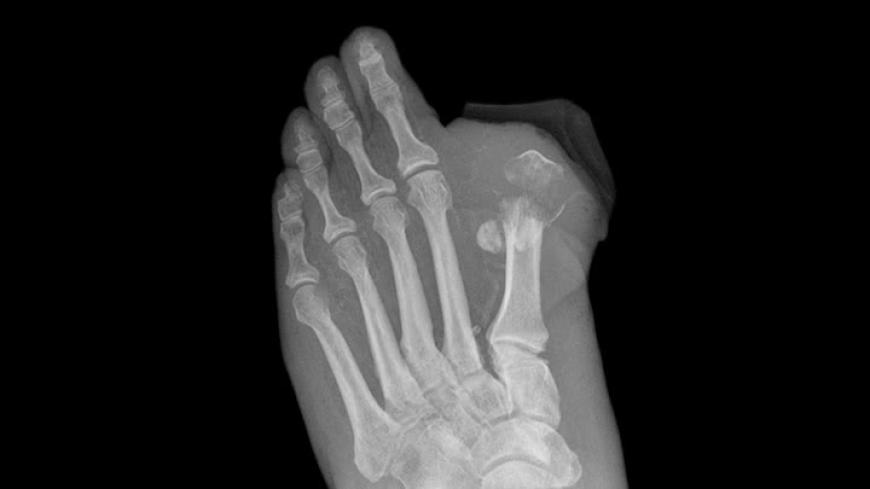

The European Medicines Agency (EMA), the European equivalent of the FDA, is reviewing a possible association between canagliflozin and amputations (mainly of the toe), which have been observed in an ongoing drug trial.

EMA started a review of canagliflozin after patients enrolled in CANVAS showed an increase in lower limb amputations. The agency says that the link between canagliflozin and lower limb amputations is not confirmed, but it is looking further into the matter.